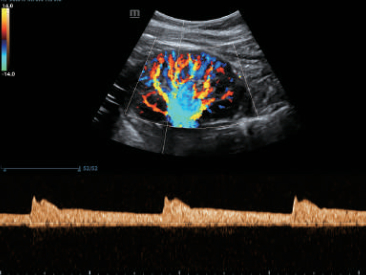

–ü―Ä–Β–¥–Ϋ–Α–Ζ–Ϋ–Α―΅–Β–Ϋ–Η–Β DC-80 EXP ―¹–Ψ―¹―²–Ψ–Η―² –≤ ―²–Ψ–Φ, ―΅―²–Ψ–±―΄ –Ω–Ψ–Φ–Ψ–≥–Α―²―¨ –£–Α–Φ ―¹–Ω–Ψ–Κ–Ψ–Ι–Ϋ–Ψ ―Ä–Β–Α–≥–Η―Ä–Ψ–≤–Α―²―¨ –Ϋ–Α ―É―¹–Μ–Ψ–Ε–Ϋ―è―é―â–Η–Β―¹―è –¥–Β–Ϋ―¨ –Ψ―²–Ψ –¥–Ϋ―è –Κ–Μ–Η–Ϋ–Η―΅–Β―¹–Κ–Η–Β –Ζ–Α–¥–Α―΅–Η, –Ω―Ä–Β–¥–Ψ―¹―²–Α–≤–Μ―è―è –Ω―Ä–Β–≤–Ψ―¹―Ö–Ψ–¥–Ϋ–Ψ–Β –Κ–Α―΅–Β―¹―²–≤–Ψ –≤–Η–Ζ―É–Α–Μ–Η–Ζ–Α―Ü–Η–Η, –Ω–Β―Ä–≤–Ψ–Κ–Μ–Α―¹―¹–Ϋ―΄–Β –Η–Ϋ―²–Β–Μ–Μ–Β–Κ―²―É–Α–Μ―¨–Ϋ―΄–Β ―Ä–Β―à–Β–Ϋ–Η―è –Η –Φ–Ϋ–Ψ–≥–Ψ–Β –¥―Ä―É–≥–Ψ–Β βÄΠ

–£–Ϋ–Β–¥―Ä–Β–Ϋ–Η–Β –≤ DC-80 EXP –¥–Α―²―΅–Η–Κ–Ψ–≤ ―¹–≤–Β―Ä―Ö–≤―΄―¹–Ψ–Κ–Ψ–Ι –Ω―Ä–Ψ–Η–Ζ–≤–Ψ–¥–Η―²–Β–Μ―¨–Ϋ–Ψ―¹―²–Η –Ψ–±–Β―¹–Ω–Β―΅–Η–≤–Α–Β―² –¥–Μ―è –£–Α―¹ –Ω―Ä–Β–≤–Ψ―¹―Ö–Ψ–¥–Ϋ–Ψ–Β –Κ–Α―΅–Β―¹―²–≤–Ψ –≤–Η–Ζ―É–Α–Μ–Η–Ζ–Α―Ü–Η–Η.

–ë–Μ–Α–≥–Ψ–¥–Α―Ä―è ―¹–Ψ―΅–Β―²–Α–Ϋ–Η―é ―²–Β―Ö–Ϋ–Ψ–Μ–Ψ–≥–Η–Η 3–Δ? (–Δ―Ä–Ψ–Ι–Ϋ–Ψ–Ι ―¹–Ψ–≥–Μ–Α―¹―É―é―â–Η–Ι ―¹–Μ–Ψ–Ι, ―²–Β―Ö–Ϋ–Ψ–Μ–Ψ–≥–Η―è –Ω–Ψ–Μ–Ϋ–Ψ―¹―²―¨―é ―Ä–Α–Ζ–¥–Β–Μ–Β–Ϋ–Ϋ―΄―Ö –Κ―Ä–Η―¹―²–Α–Μ–Μ–Ψ–≤, ―²–Β―Ä–Φ–Ψ–Κ–Ψ–Ϋ―²―Ä–Ψ–Μ―¨ –Α–Κ―É―¹―²–Η―΅–Β―¹–Κ–Ψ–Ι –Μ–Η–Ϋ–Ζ―΄) –Η –Φ–Ψ–Ϋ–Ψ–Κ―Ä–Η―¹―²–Α–Μ–Μ–Η―΅–Β―¹–Κ–Η―Ö –¥–Α―²―΅–Η–Κ–Ψ–≤ –Ψ–±–Β―¹–Ω–Β―΅–Η–≤–Α–Β―²―¹―è –Κ–Α–Κ –±–Ψ–Μ–Β–Β –≤―΄―¹–Ψ–Κ–Α―è ―Ä–Α–Ζ―Ä–Β―à–Α―é―â–Α―è, ―²–Α–Κ –Η –Ω―Ä–Ψ–Ϋ–Η–Κ–Α―é―â–Α―è ―¹–Ω–Ψ―¹–Ψ–±–Ϋ–Ψ―¹―²―¨, –≤ ―Ä–Β–Ζ―É–Μ―¨―²–Α―²–Β ―΅–Β–≥–Ψ ―Ä–Β―à–Α–Β―²―¹―è –Ω―Ä–Ψ–±–Μ–Β–Φ–Α –Η―¹―¹–Μ–Β–¥–Ψ–≤–Α–Ϋ–Η–Ι ―²–Β―Ö–Ϋ–Η―΅–Β―¹–Κ–Η ―¹–Μ–Ψ–Ε–Ϋ―΄―Ö –Ω–Α―Ü–Η–Β–Ϋ―²–Ψ–≤.

–Θ–Μ―¨―²―Ä–Α–Μ–Β–≥–Κ–Η–Ι –Η –≤―΄―¹–Ψ–Κ–Ψ–Ω–Μ–Ψ―²–Ϋ―΄–Ι –Ψ–±―ä–Β–Φ–Ϋ―΄–Ι –¥–Α―²―΅–Η–Κ –Ψ–±–Β―¹–Ω–Β―΅–Η–≤–Α–Β―² –Ω―Ä–Β–≤–Ψ―¹―Ö–Ψ–¥–Ϋ–Ψ–Β –Κ–Α―΅–Β―¹―²–≤–Ψ –≤–Η–Ζ―É–Α–Μ–Η–Ζ–Α―Ü–Η–Η –≤ –Α–Κ―É―à–Β―Ä―¹―²–≤–Β –≤ ―Ä–Β–Ε–Η–Φ–Α―Ö 2D, –Π–î–ö, 3D/4D –¥–Μ―è –±–Ψ–Μ―¨―à–Β–Ι –¥–Η–Α–≥–Ϋ–Ψ―¹―²–Η―΅–Β―¹–Κ–Ψ–Ι ―É–≤–Β―Ä–Β–Ϋ–Ϋ–Ψ―¹―²–Η –Η –Ω–Ψ–≤―΄―à–Β–Ϋ–Η―è –Κ–Α―΅–Β―¹―²–≤–Α –Η―¹―¹–Μ–Β–¥–Ψ–≤–Α–Ϋ–Η―è;